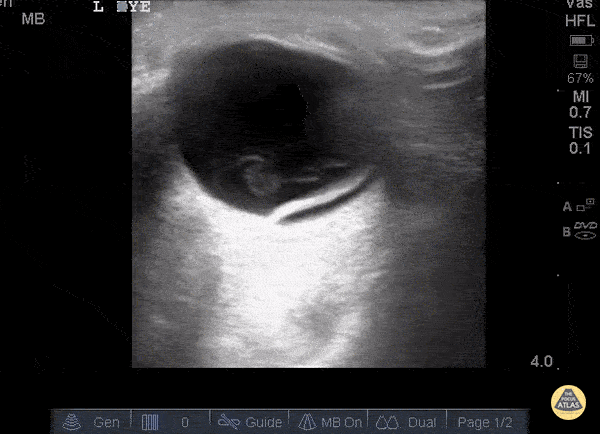

Orbital - Retinal Detachment

Here a hyperechoic linear density is seen arising from the location of the fundus, indicating retinal detachment. Posterior vitreous detachment and vitreous hemorrhage can look similar to retinal detachment. Given the imminent risk of blindness in these conditions it is essential to identify them as soon as possible. POCUS is an excellent way to do so given the time and skills required to perform a proper fundoscopic exam. Literature has shown sensitivity for this test to be 97-100% and specificity 83-100%. So next time ask yourself... is your fundoscopic exam that good? Sukh Singh, MD